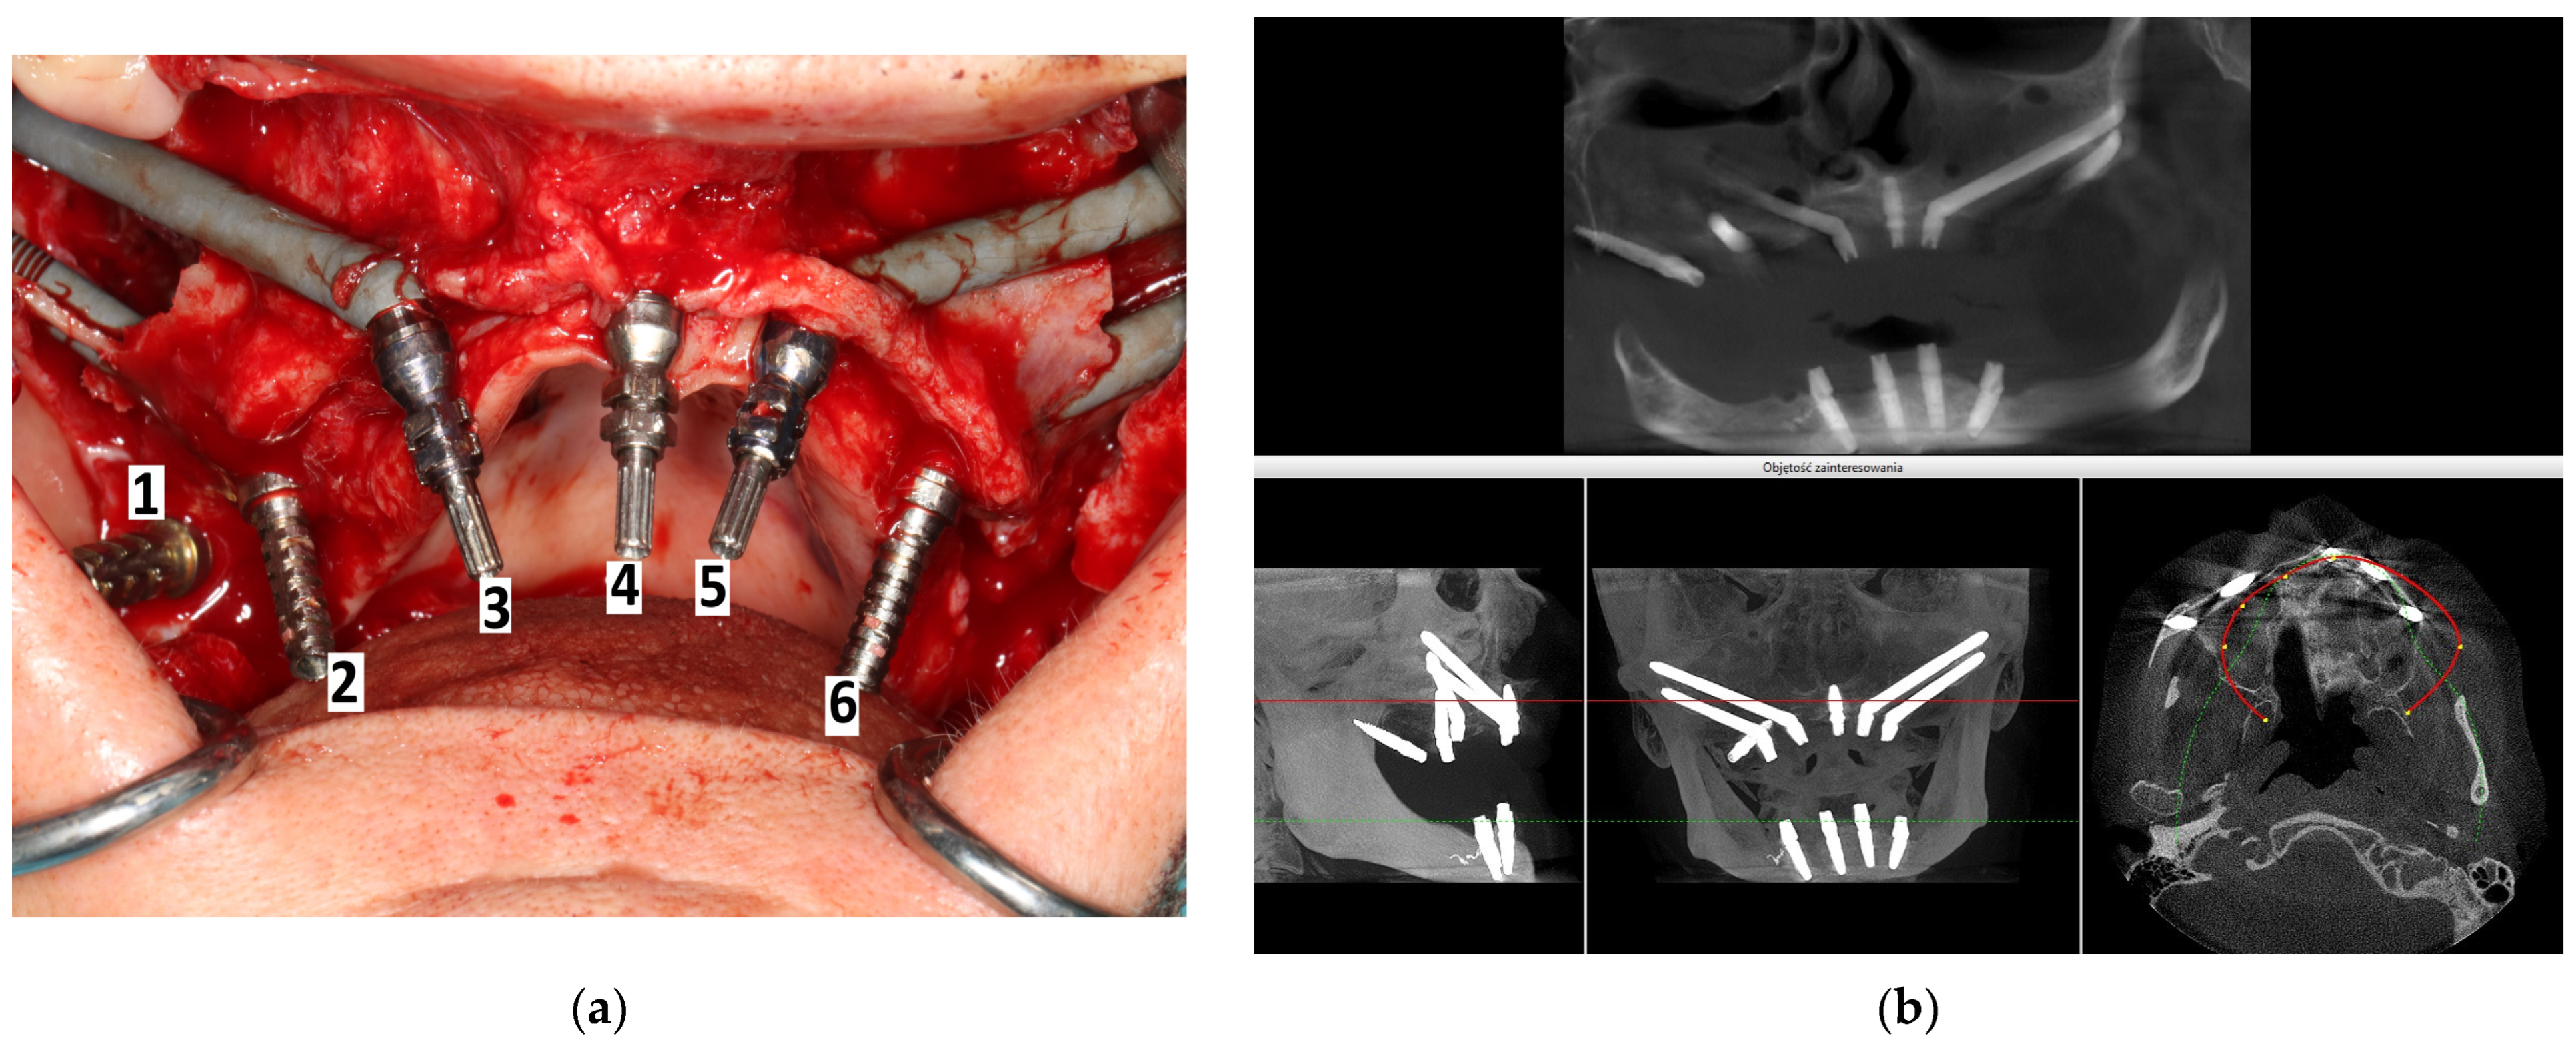

2. Materials and Methods

- Group 1 (14 patients) received 4 zygomatic implants along with 1 or 2 conventional implants.

- Group 2 (15 patients) received 4 zygomatic implants exclusively.

- Group 3 (46 patients) received 2 zygomatic implants and 4 conventional implants.

2.2. Surgery